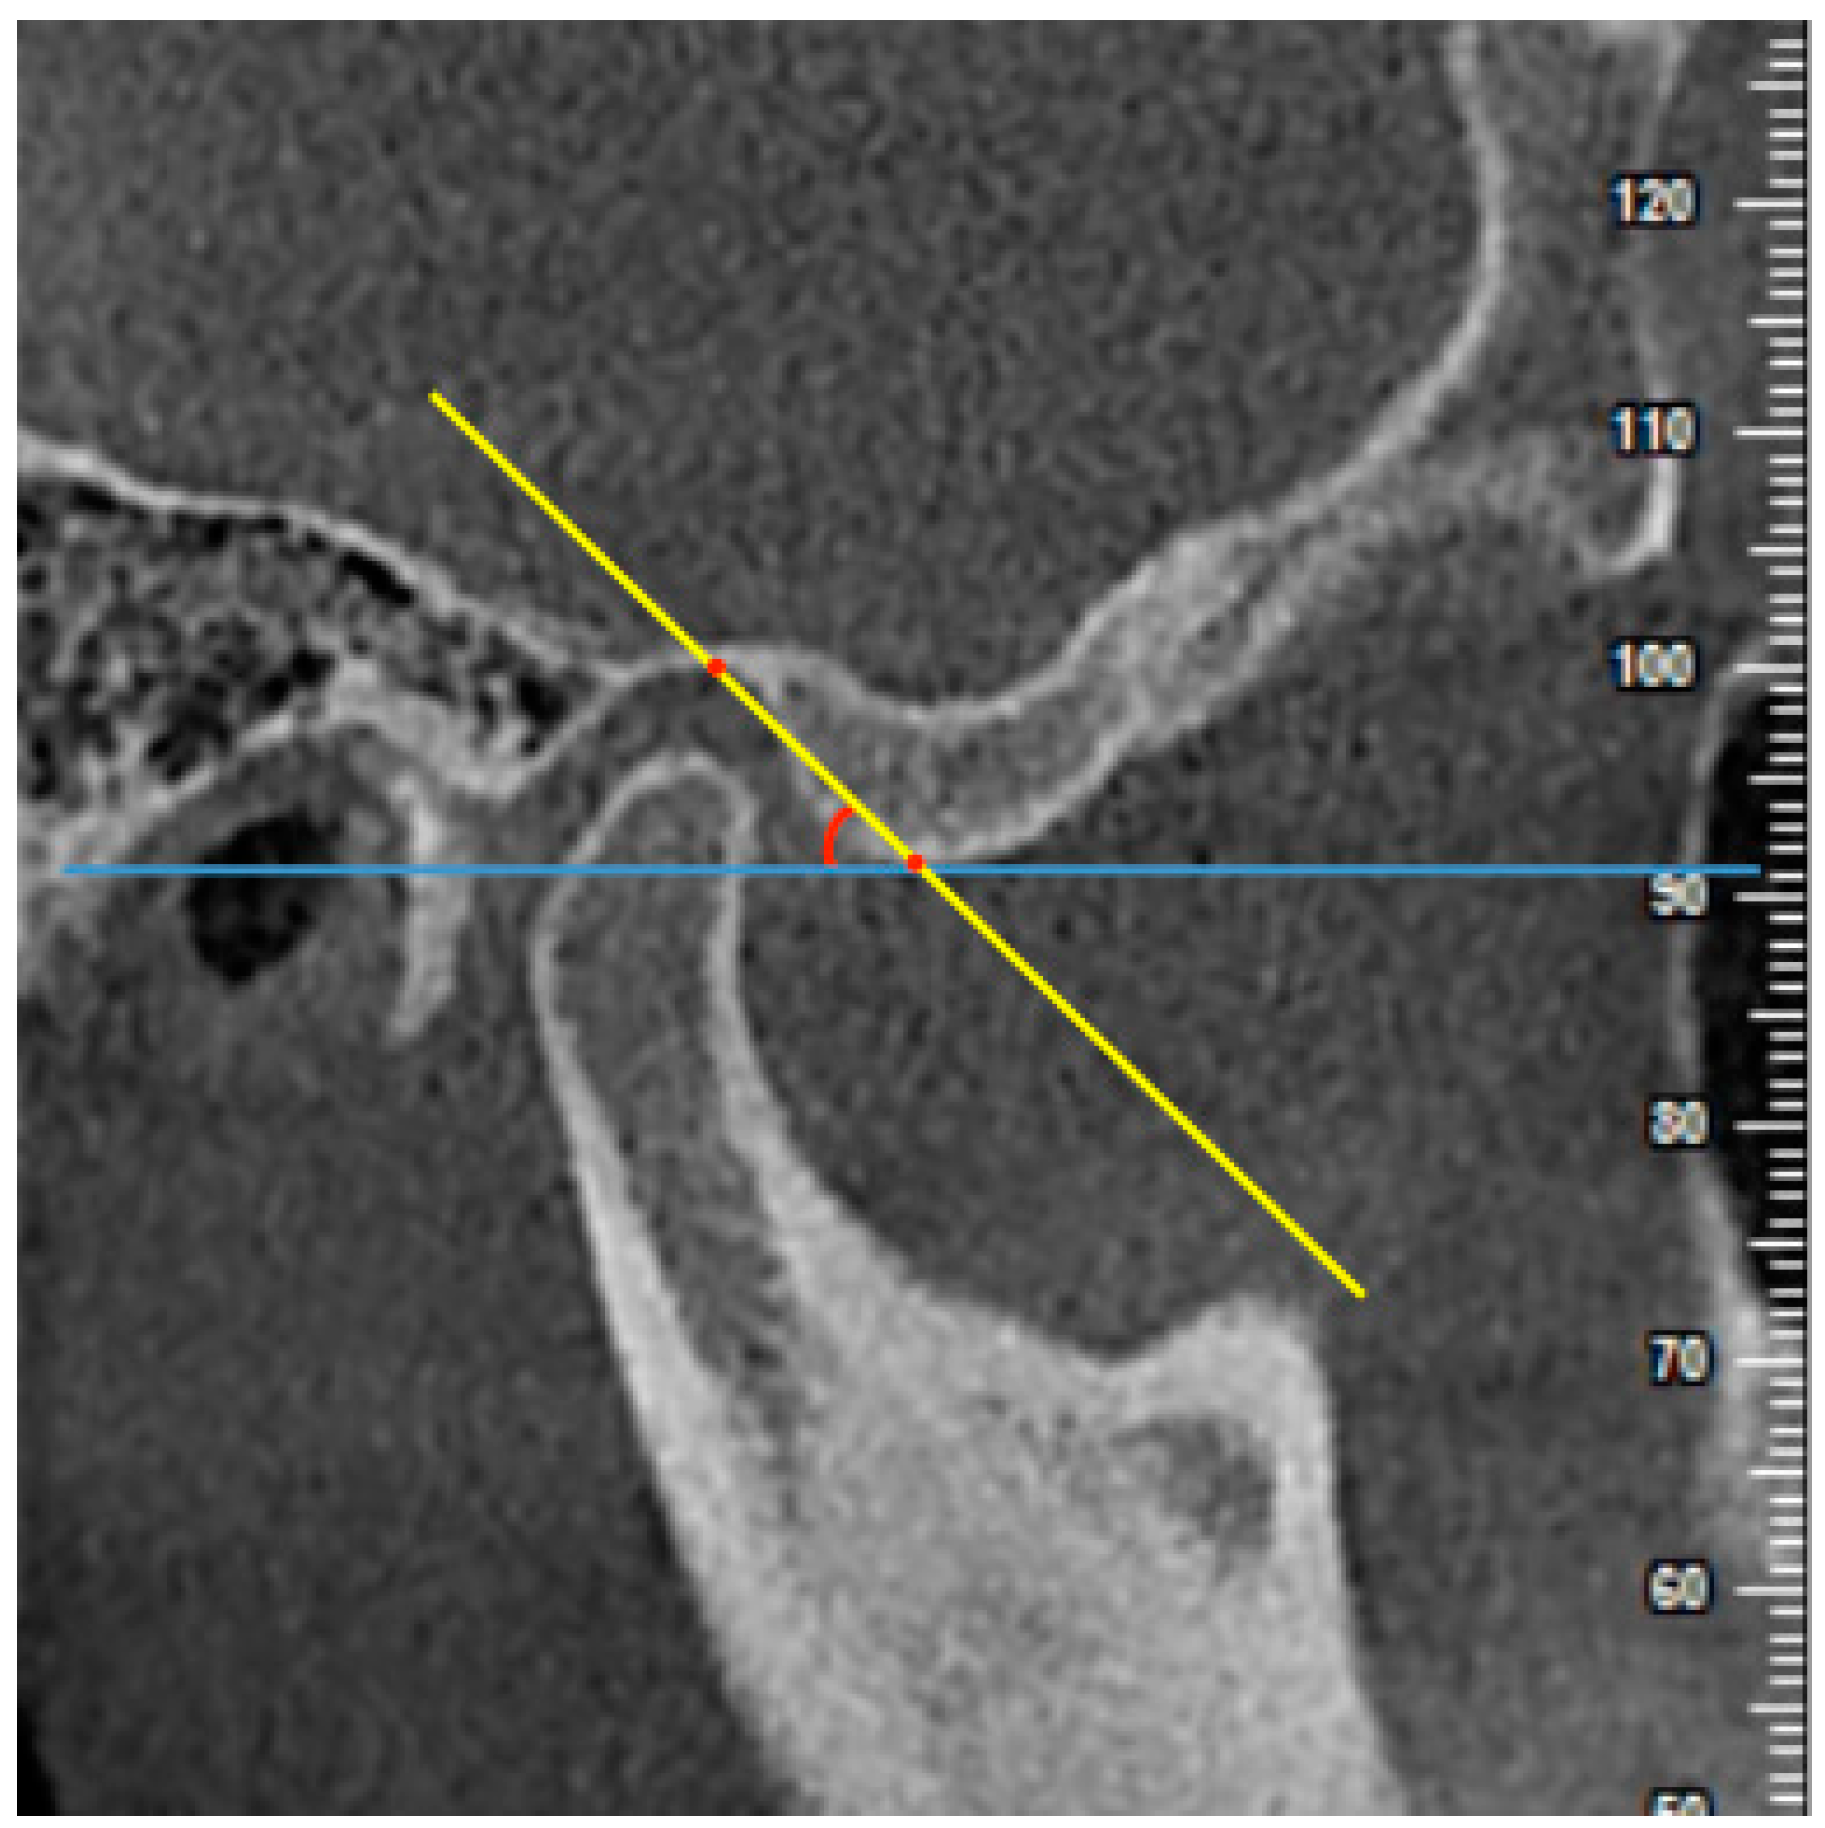

2.4. Measurements